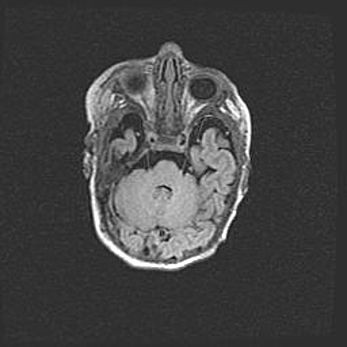

Подострая гематома правой гемисферы мозжечка.

Наружная гидроцефалия.

Возраст: 15 дней

Вес: 3100 г

Пол: женский

Окружность головы: 37 см

Срок гестации: 35-36 недель

При открытой наружной форме гидроцефалии у новорожденных расширяются и переполняются субарахноидные пространства.

Кровоизлияния в мозжечок имеют две клинико-анатомические формы: полушарные гематомы и кровоизлияния в червь.

К появлению этой патологии может привести: повреждения головного мозга, возникающие в результате асфиксии и гипоксии плода при беременности, или травмы во время родов. Редко гематома мозжечка может быть результатом первичной коагулопатии и сосудистой мальформации, диссеминированном внутрисосудистом свертывании, изоиммунной тромбоцитопении.